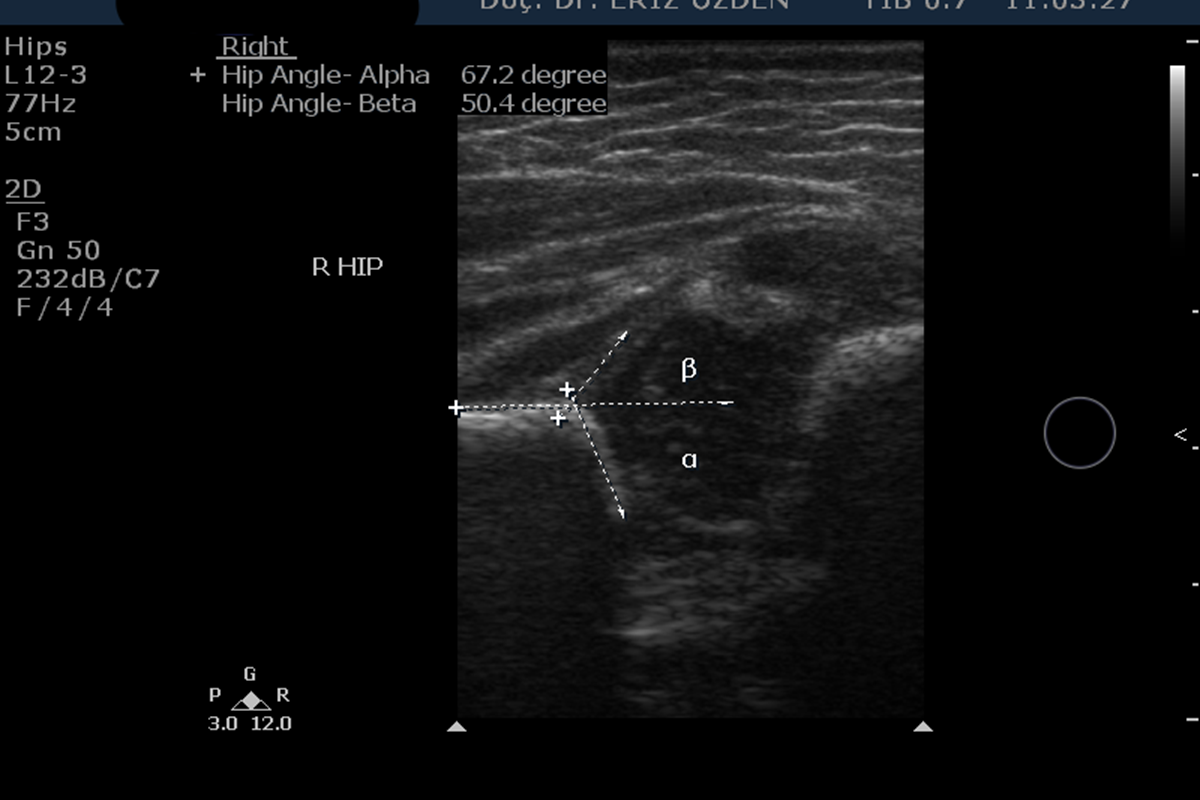

Bebeklerde Kalça Ultrasonu Sonucu Ne Olmalı? Bu incelemede bebeğin her iki kalçasındaki eklem yüzeylerinin açıları ölçülür. Bu yüzeylerin, femur adı verilen kalça kemiğinin baş kısmını tamamen kapsayacak kadar gelişmiş olması gerekmektedir. Yapılan açı ölçümlerinden en önemlisi alfa açısı ölçümüdür ve 60 dereceye eşit veya üzerinde olmalıdır. İki aylık bir bebekte alfa açısı ölçümü 50- 60 derece arasında ise, bir ay kadar sonra ikinci bir ultrason kontrolü daha yapılır. Ancak 50 derece altındaki alfa açısı ölçümlerinde vakit geçirmeden tedaviye başlanması önerilmektedir. Alfa açısı ölçümlerine ek olarak, beta açısı ve kapsama oranı denilen ek ölçümler de yapılmaktadır. Tüm bu ölçümlerin sonuçlarına göre Graf sınıflaması adı verilen, Ultrason’a göre belirlenen bir sınıflama yapılır. Graf Tip 1 normal inceleme demektir.